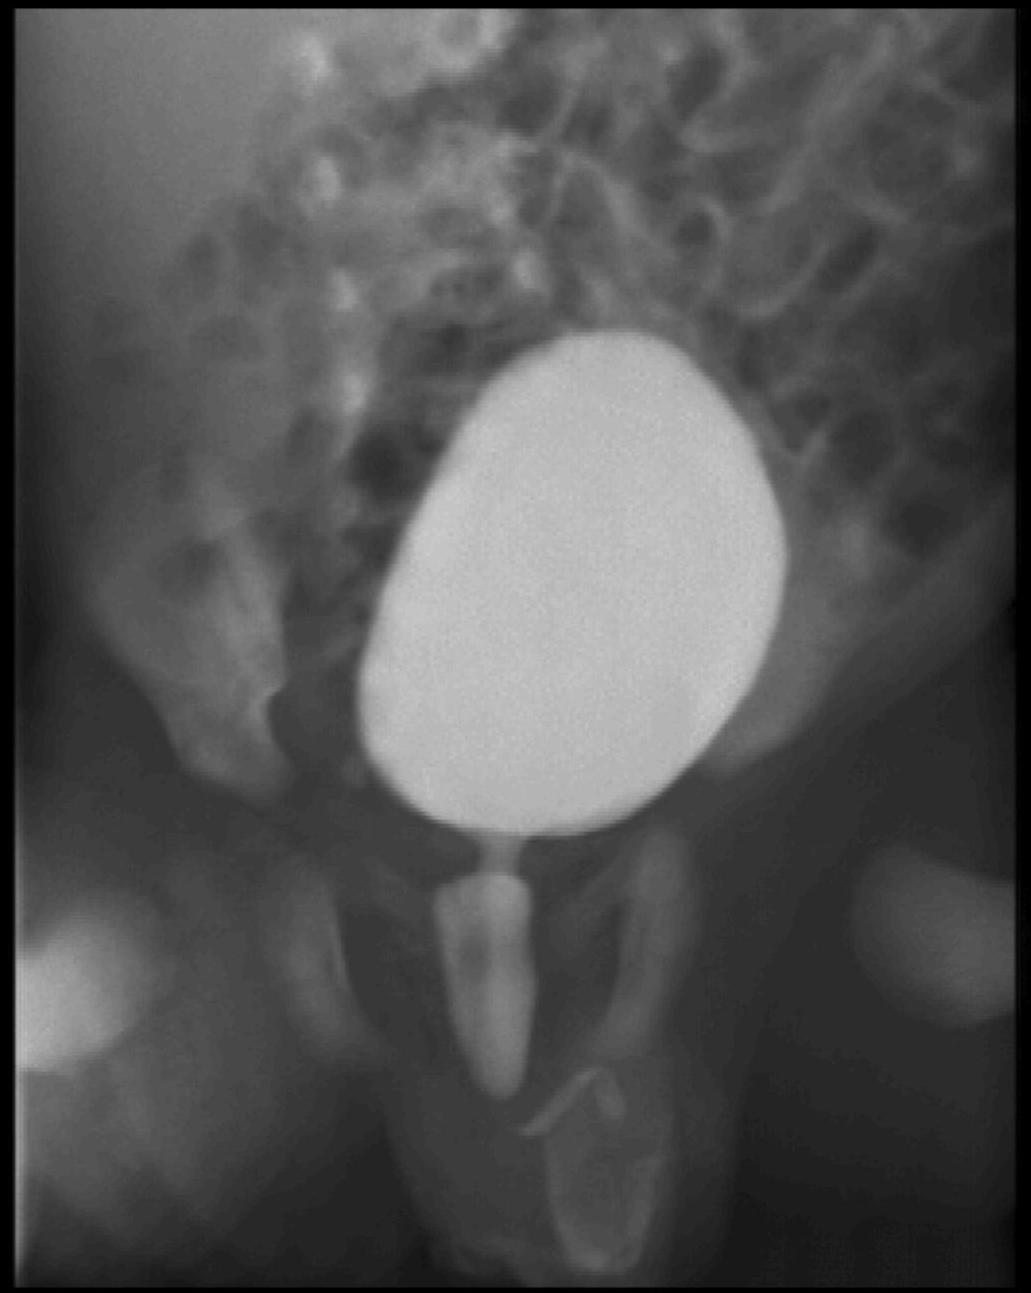

Distal urethral valve (subvesical obstruction). It is the most severe form of obstructive uropathy. In newborn boys the valve dysfunction can lead to bilateral obstruction with hydronephrosis and hydroureter. Urination can only occur intermittently. The bladder wall is thickened, trabecular and reflux is frequent. The proximal urethra is distended as well.

23. Miction cystourethrography. A small diverticula is seen on the right side, the proximal urethra is dilated, beneath is a filling defect. Subvesical obstruction, dorsal urethral valve.